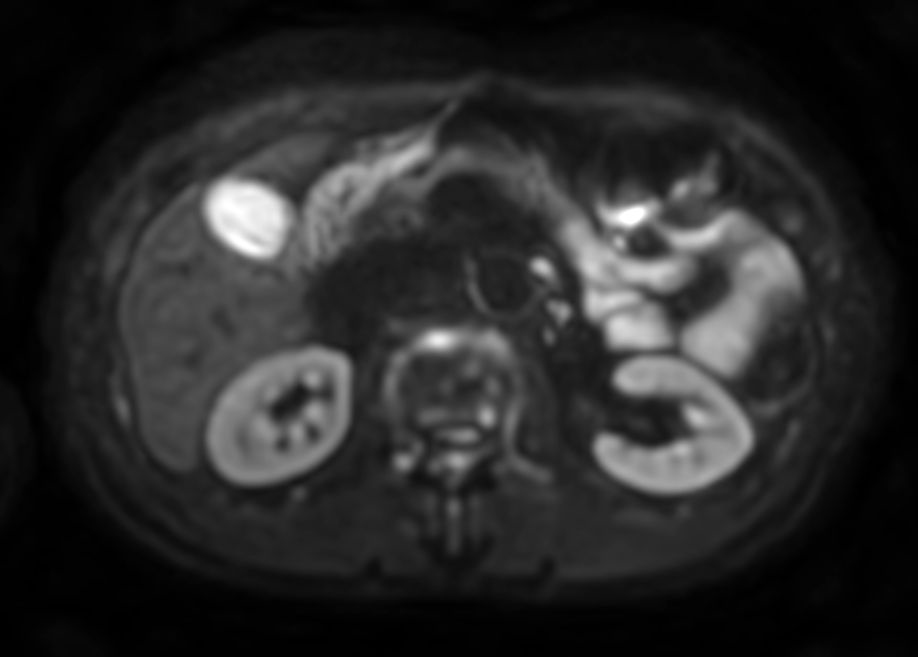

Diffusion - b800

-

Diffusion - b800 (ADC)